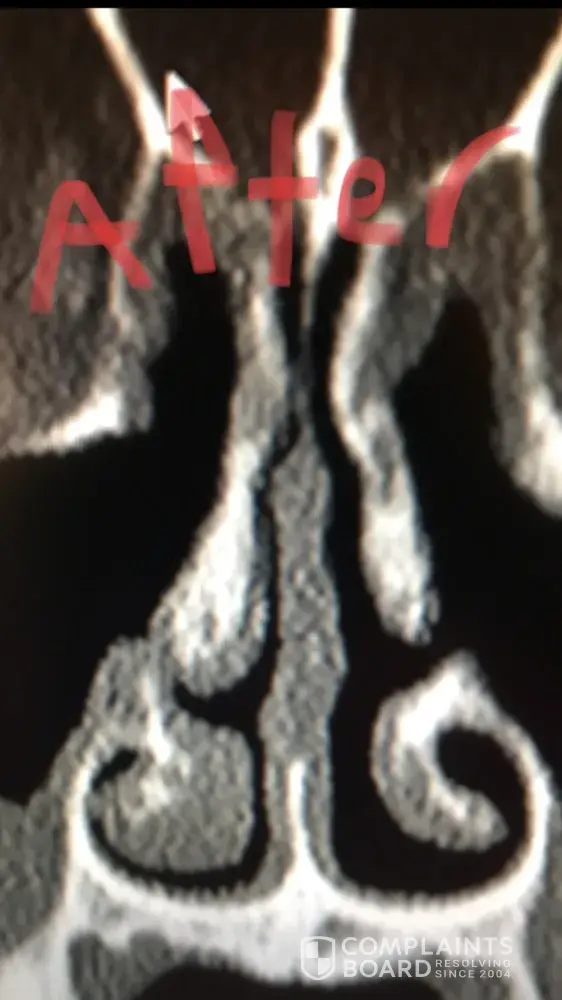

For people reading this, I have included x-ray images of the inside of my nose, before and after my surgery with him. As you can see from these images, my nasal airway was equally open on both sides, before surgery, and the septoplasty didn't need to be done. By performing it, he severely narrowed the right side of my nasal airway.

Dr Raviv performed two surgeries on me: endoscopic sinus surgery (where they widen the sinus passages), and septoplasty (where they straighten the septum). The septoplasty, however was completely unnecessary, and severely narrowed the right side of my nasal airway. For people reading this, I have included x-ray images of my sinuses, before and after my surgery with Dr. Raviv. As you can see from the surgery, my airway was much more open, and equal on both sides, before my surgery with him.